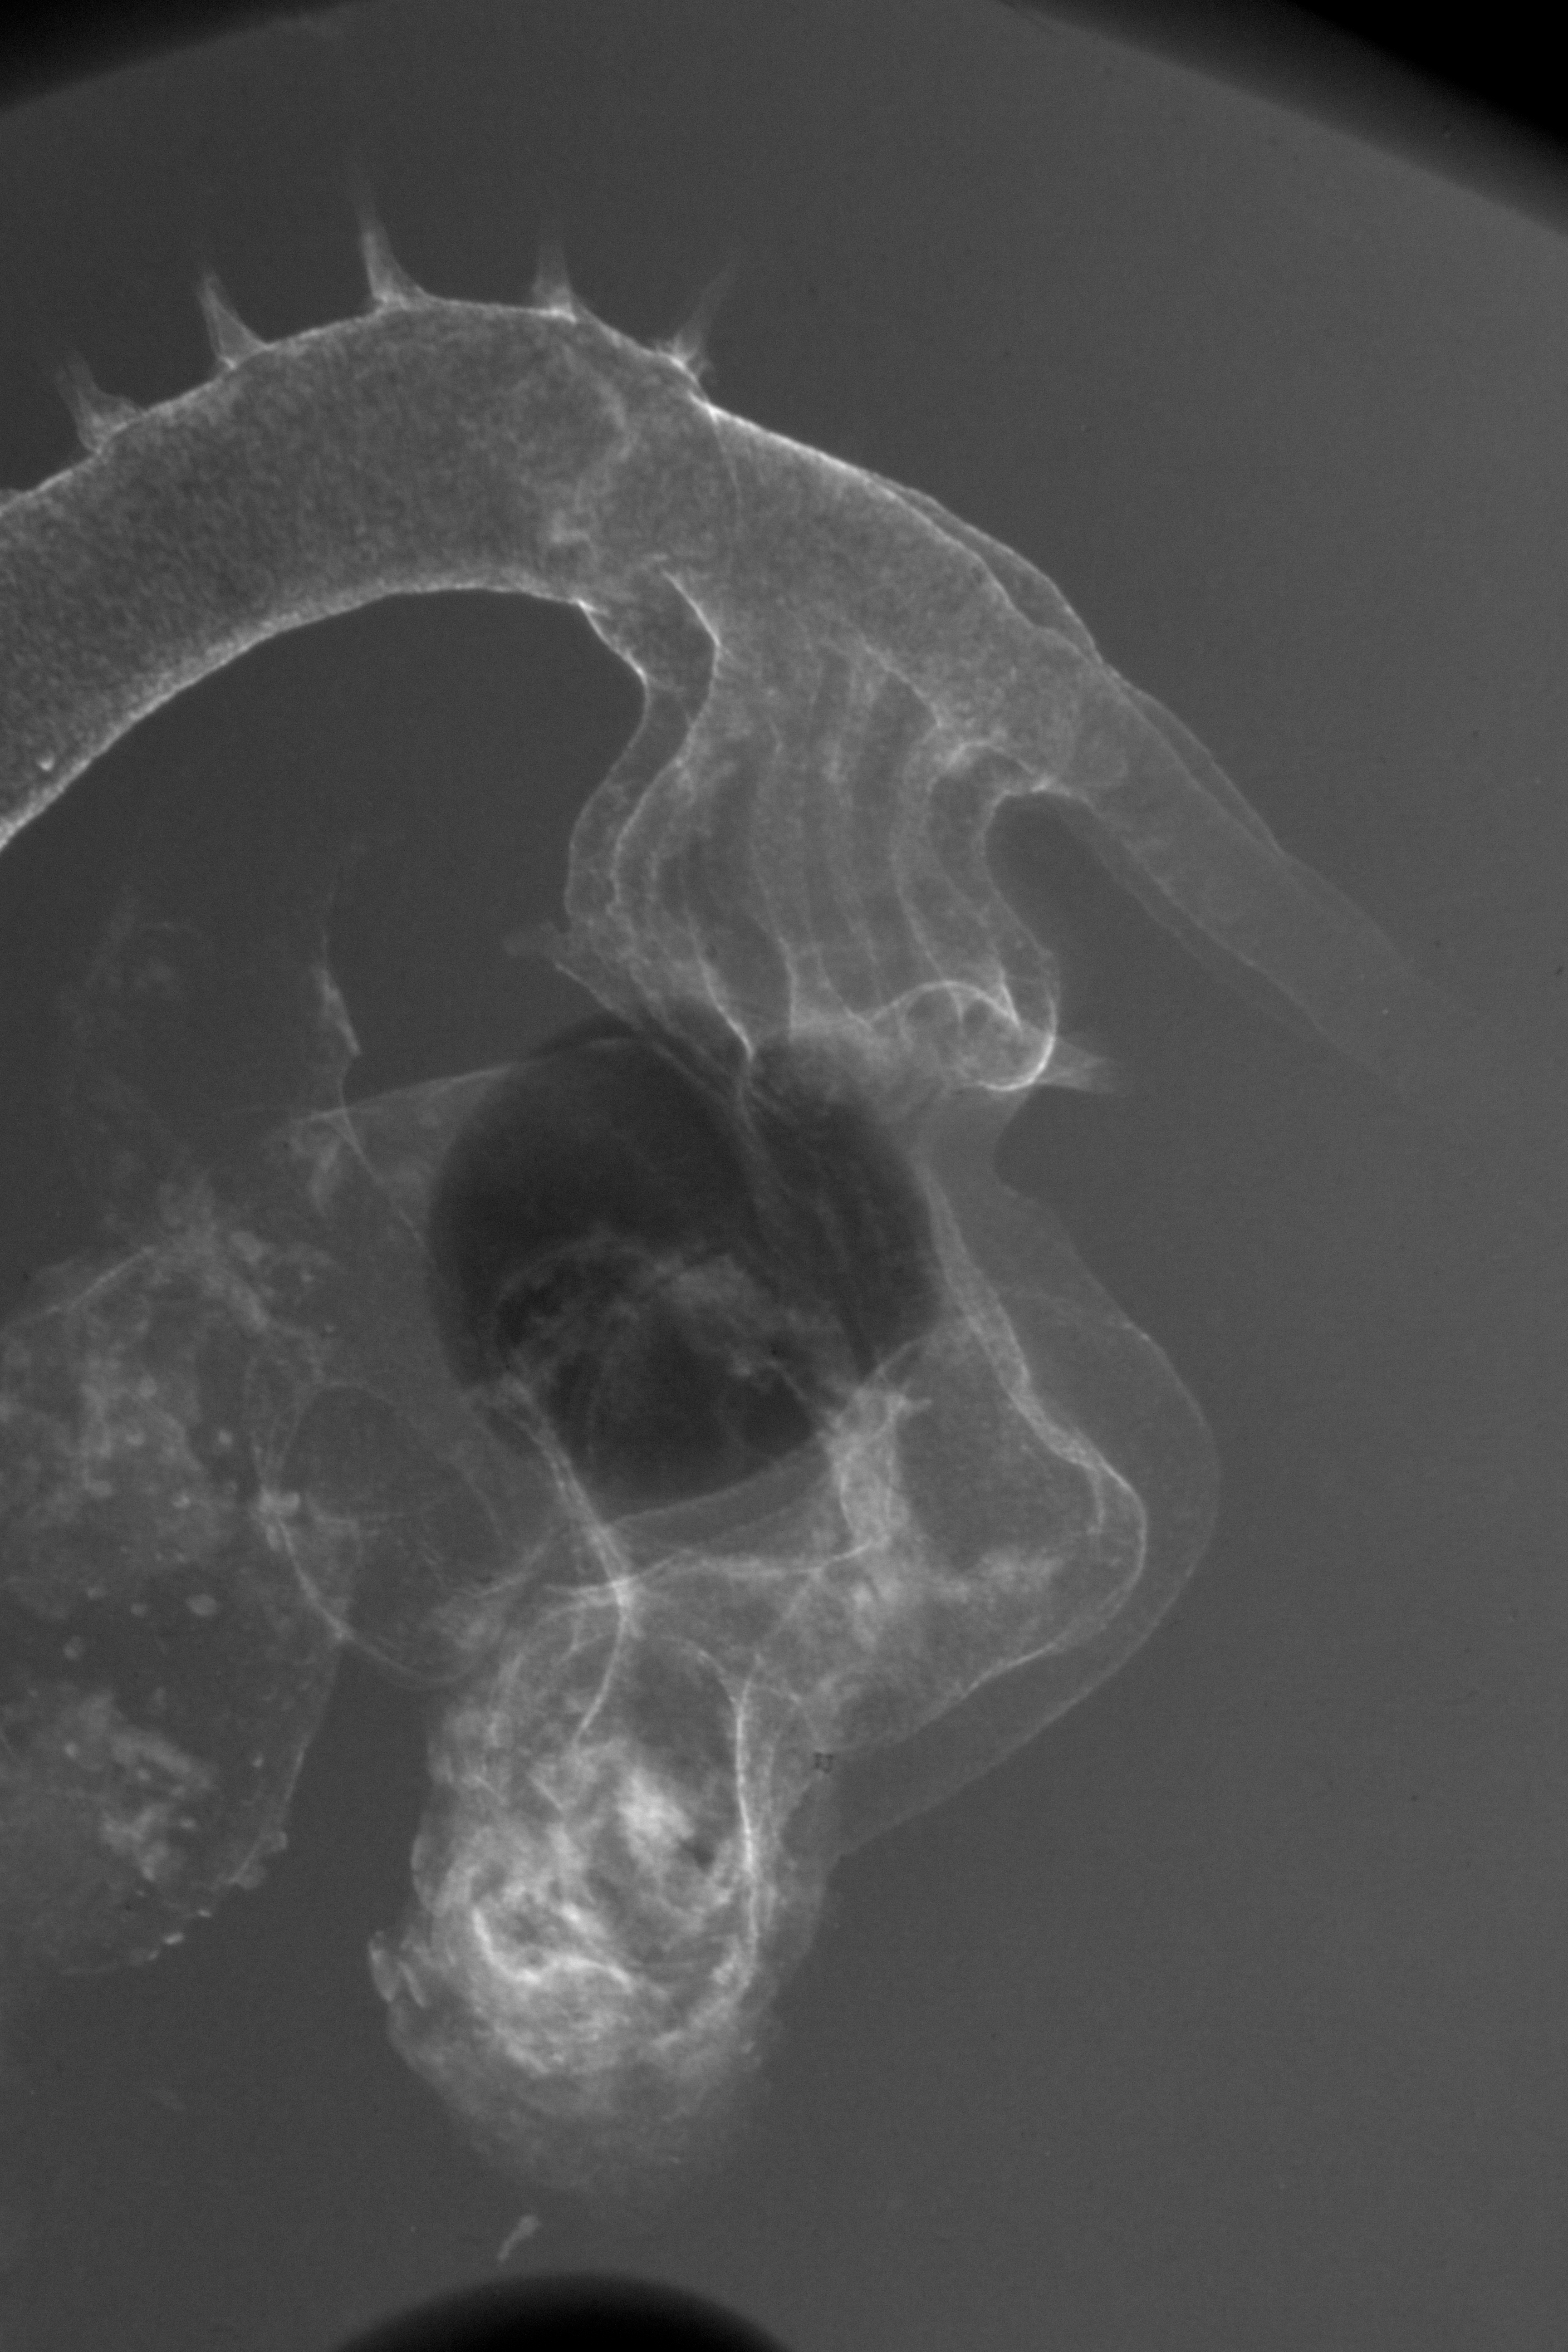

Chick Embryo Microangiography

Hamburger-Hamilton (HH) Stage 21 (approx. 3.5 days)

X-Ray Micrographs